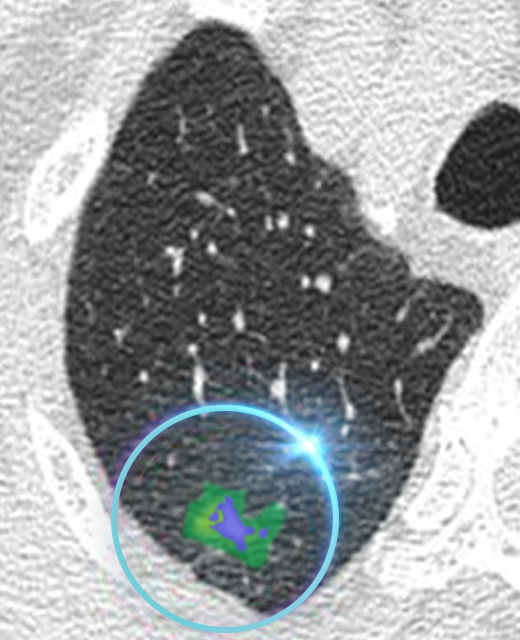

Our AI technology processes the low-dose scan and compares them to similar scans in Fujifilm’s vast library of imaging data. This enables us to sharpen the low-dose image and identify problems that would be missed by the naked eye.

AI Enhanced Ultra Low-Dose Scan

Our AI technology is able to sharpen the quality of the ultra-low dose scan to assist the doctor in early detection.

REiLi is our AI technology that uses deep learning and Fujifilm’s extensive image processing database to detect abnormalities automatically. This helps doctors accurately recognize the affected area and reduce the time taken by radiologists to interpret the scan.